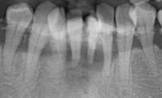

症例1

長期に渡る清掃不良のため、根元に真っ黒な歯石が厚く付着しています。左下 1 番(向かって右の歯)は完全に位置がずれ浮いてしまっています。

左の写真のレントゲン像です。右下 2 番から左下 2 番は抜歯となりました。右下 3 、 4 と左下 3 、 4 は辛うじて保存可能でした。